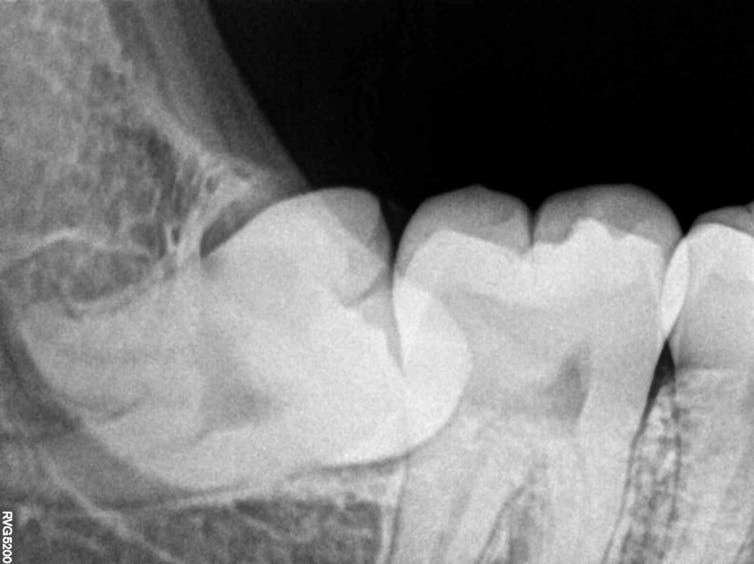

Sometimes, due to lack of space, wisdom teeth can get stuck inside the jawbone and never fully come up – or they only partially emerge.

A so-called impacted wisdom tooth happens more often in the lower jaw than in the upper jaw. In cases where wisdom teeth are only partially up, people can sometimes experience pain, tooth decay or gum inflammation, which is why they have them pulled by a dentist.

But wisdom teeth don’t usually need to be removed if they are fully erupted in the mouth, positioned correctly and healthy.

Dentists can examine your mouth to see if your wisdom teeth are present, or look at X-ray pictures of your jaw if these last molars haven’t yet emerged and you suspect they may be impacted.